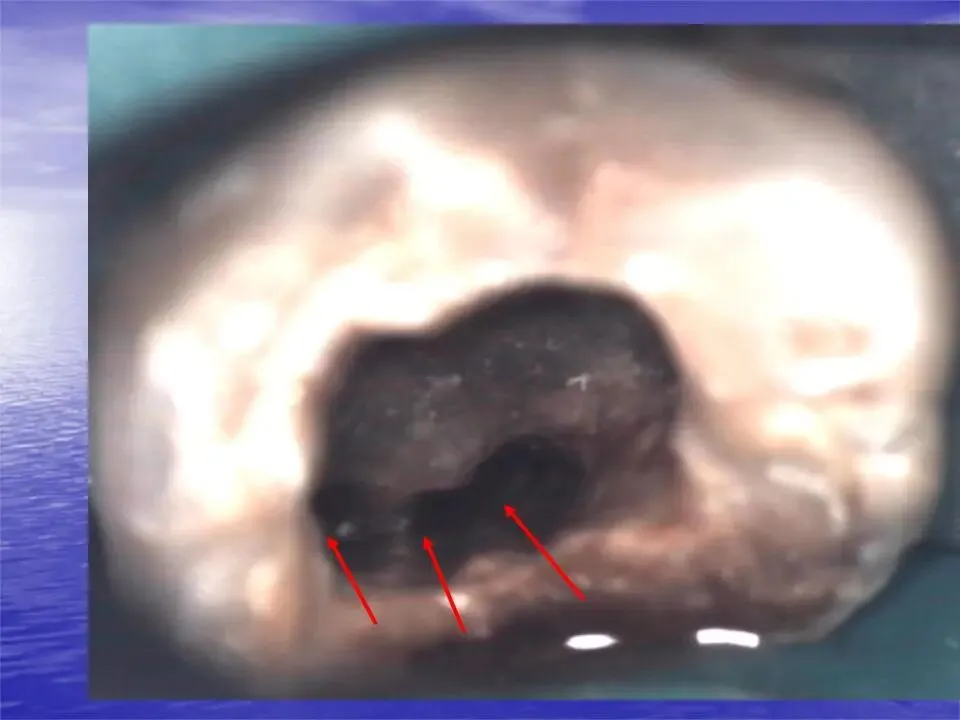

④ 机械预备后,最终冲洗的冲洗液量应大于5 mL/根管。存在感染的根管建议至少预备至30#,以便30#冲洗针能够达到足够深度,确保冲洗液在根尖1/3区域的有效作用,清除根尖区域牙髓组织、碎屑和感染物质。